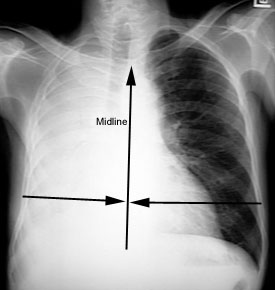

Alterations in proportion of Left and Right Lung

The right lung is approximately 55% and left lung 45%. In atelectasis this apportionment will change and can be a clue to recognition of atelectasis. In a given case one or more of these features will alert you to the presence of atelectasis. Note in this patient with RLL atelectasis overall right lung is smaller than left lung.

Hemithorax asymmetry

In normals right and left henithorax are equal in size. The size of hemithorax will be asymmetrical and smaller on the side of atelectasis.